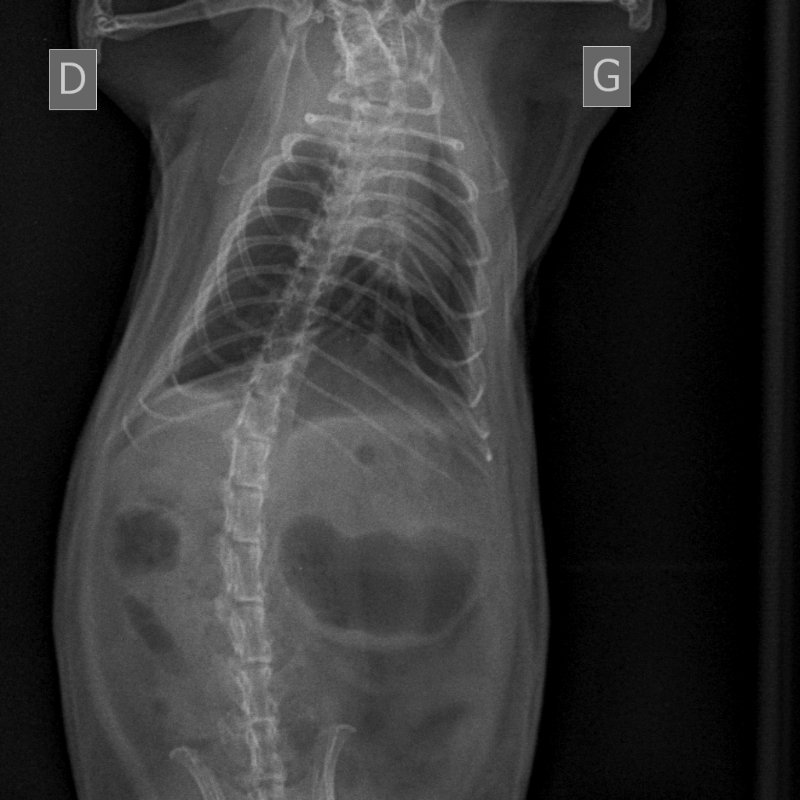

Fin mars j'ai trouvé la respiration de Kobayashi Maru étrange. Elle était un peu plus rapide et superficielle. Dans le doute, j'ai pris RDV pour une radio lundi 4.

Le WE juste avant, il a commencé à faire de légers bruits respiratoire, et sa respiration est devenue clairement plus rapide. À la pesée, je me suis aperçue qu'il avait de nouveau perdu du poids (390g).

À la radio, pour reprendre Artefact "c'est pas si pire", mais ça pourrait être mieux. On trouve quelques foyers. On part avec le véto sur 10 jours de doxycycline, 5mg/kg/12h, en PO.

Les radios d'hier :

NAC-THORAX PROFIL-04_04_2022-14_56_20-547.JPEG

NAC-ABDOMEN FACE NORMAL-04_04_2022-14_56_20-157.JPEG